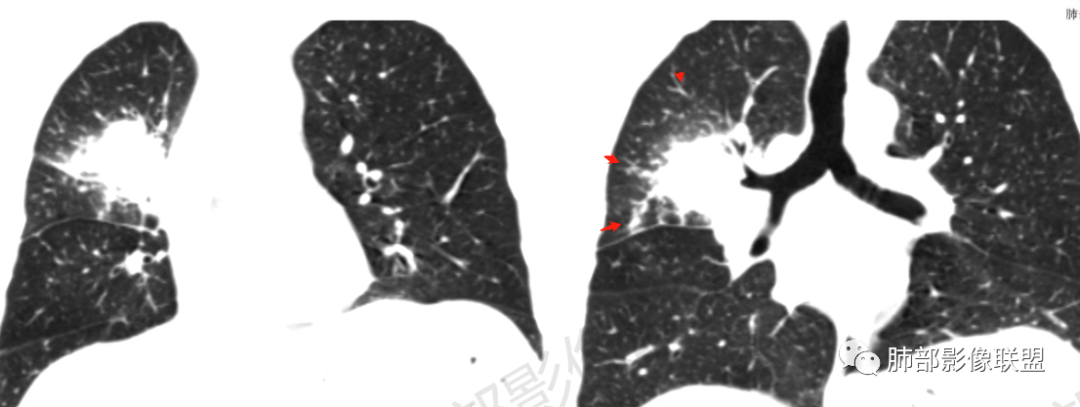

环形强化

坏死区几乎是寸草不生

1、坏死区内寸草不生;2、病灶环形强化;3、远端树芽和结节;4、远端不是阻塞性炎症,而是树芽和结节,右肺上叶前后段都有,后段为主,而堵塞的支气管应该是前段;这些树芽的位置不是堵塞支气管的责任区;5、支气管不是突然截断堵塞,而是逐渐狭窄;6、纵隔淋巴结是椭圆形增大,内有坏死,不是肿瘤的圆形饱满;7、支气管周围粘液样坏死,符合仙人掌结核改变;

1、支气管堵塞:这个病例的支气管不是突然截断,而是逐渐狭窄的;

2、湖泊样坏死:这个病例其实不是湖泊样坏死。湖泊样坏死边界不清,周围有水草样改变;这个病例的坏死更像水库,不是湖泊,坏死区边界清楚,里面寸草不生;

3、阻塞性炎症:这个病例远端的散在病灶分布与责任支气管不符,所以不是阻塞性炎症,应该是树芽;

4、纵隔淋巴结肿大:这个病例的淋巴结肿大,不是圆形饱满,而是椭圆形,中间坏死。

所以,这个病例应先考虑炎性病变,以结核可能性大。慢性非特异性炎症伴脓肿形成,也可以这样的影像改变,但解释不了周围的树芽和结节。

再解释一下水库与湖泊的区别:

水库:是人工的,边缘是石头彻的大坝(环形强化类似大坝),坝缘没草长,边界清楚。

湖泊:是天然的,周围没有环形强化的大坝,是逐渐过渡到强化区的,边缘可有细小血管或者坏死不彻底的肿瘤区。